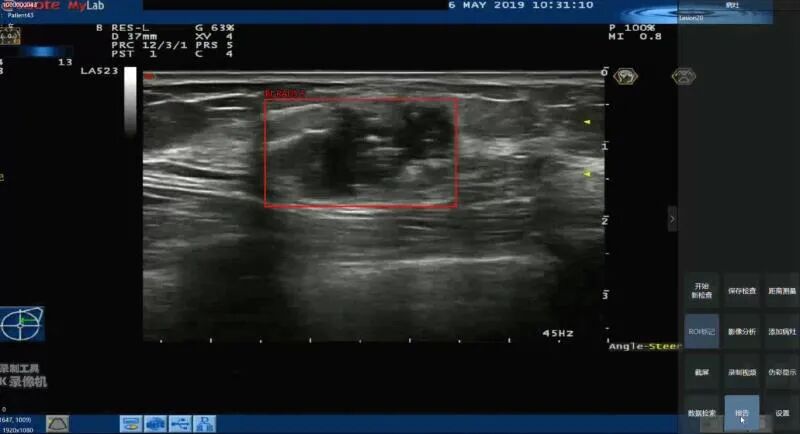

近期医准智能发布了乳腺超声智能检测系统,该系统将二维静态图像扩展到实时视频,与临床实际操作更贴近,医生可以实时看到结果。

在使用上,该系统不需要对设备改动,且不需要调整现有工作流程,在医生扫查病人的同时,AI服务器进行实时分析,并在界面进行标记提示,对于仅毫秒级闪现的病灶也能精准抓取,能够有效的避免医生由于视觉疲劳以及视觉敏感度不够而产生的漏诊。